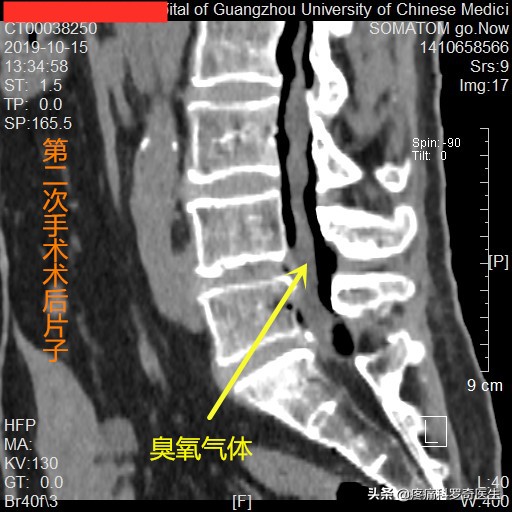

第二次住院,术后臭氧气体扩散情况

4个月后,患者第二次住院做微创手术,同样的地方注射臭氧气体松解椎管内的神经粘连,我们可以看到臭氧气体已经扩散到了整个腰椎,说明,椎管内大面积的脊髓和神经根粘连已经得到了很好的松解,虽然患者的突出物并没有缩小多少,钙化物还是没变,但患者的下肢症状基本消除了。